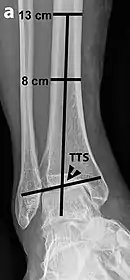

Tibiotalar surface angle (TTS)

Varus or valgus deformity, if suspected, can be measured with the frontal tibiotalar surface angle (TTS), formed by the mid-longitudinal tibial axis (such as through a line bisecting the tibia at 8 and 13 cm above the tibial plafond) and the talar surface.[24] An angle of less than 84 degrees is regarded as talipes varus, and an angle of more than 94 degrees is regarded as talipes valgus.[25]